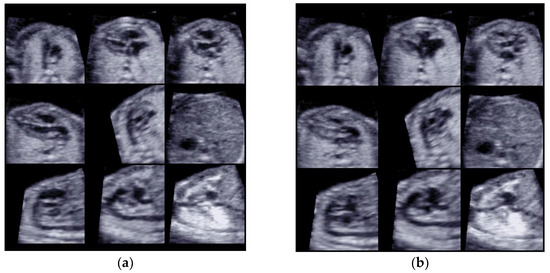

One or more STIC volumes (totally 20) were acquired. From the STIC volumes determined to be appropriate using STICLoop™, only a single volume per patient was selected for the analysis using the FINE method. When there were multiple appropriate STIC volumes available per fetus, we chose the dataset of highest quality. Nine cardiac diagnostic planes in a single template with the additional feature of automatic labeling through intelligent navigation were extracted (Figure 1a,b).

Figure 1.

(a) Diagnostic planes with FINE in the systolic cardiac phase; 9 planes were used for the analysis. (b) Diagnostic planes with FINE in the diastolic cardiac phase; 9 planes were used for the analysis.